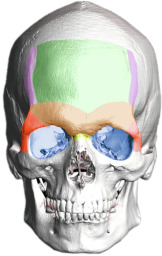

These differentiating features appear in the frontonasoorbital complex, the nose, the malar region, the upper lip, the jaw and chin complex, and the thyroid cartilage ( Fig. 8.1 ). The development of these structures under hormonal influence is not reversible, and thus these features, which determine a significant part of an individual’s facial gender, can only be approached and modified using surgery, always respecting the intrinsic architecture and anatomy of the craniofacial skeleton.

This area is quite possibly the greatest determinant of facial gender. The region encompasses the forehead surface, the supraorbital ridge (frontal bossing), the eye sockets, the frontomalar buttresses, the temporal ridges, and the frontonasal transition ( Fig. 8.2 ). The supraorbital ridge is almost invariably much more strongly developed in the male than in the female, although, typically, all of these areas are more pronounced and have greater bone volume in the male skeleton than in the female skeleton. The forehead contour in the female is higher, smoother, more vertical, and may be rounded to the point of forward protrusion. It determines the position of the eyebrows and the positioning of the periorbital soft tissues like the eyelids.

To better understand the jaw, it needs to be divided into the mandibular body, the mandibular angle and the ascending ramus ( Fig. 8.3 ). Generally speaking, the male jaw is larger, with greater body height and a broader ascending ramus. The mandibular angle formed by the body and ramus tends to be more acute in males, at times with everted gonial angles. The greater bone volume and vertical height are important factors when planning mandibular reshaping techniques in FGCS.

The male chin tends to be more square-shaped, with more pronounced and defined transitions between the chin and mandibular body, greater bone volume, and a more significant vertical dimension. Gender does not necessarily determine the position of the chin; that is, it is possible to find retro-positioned or over-projected chins in both men and women. However, a well-defined and projected chin may improve the overall aesthetics of the jaw-chin region.